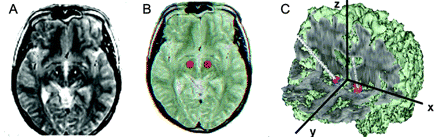

STN-DBS激活目标区域在帕金森病:正研究

作者显示丘脑核的激活和globus螺旋体帕金森病病人脑深部刺激。这些数据揭示了基本机制在人类的大脑和脑深部电刺激行动有助于未来的进步有益的治疗帕金森病晚期患者。